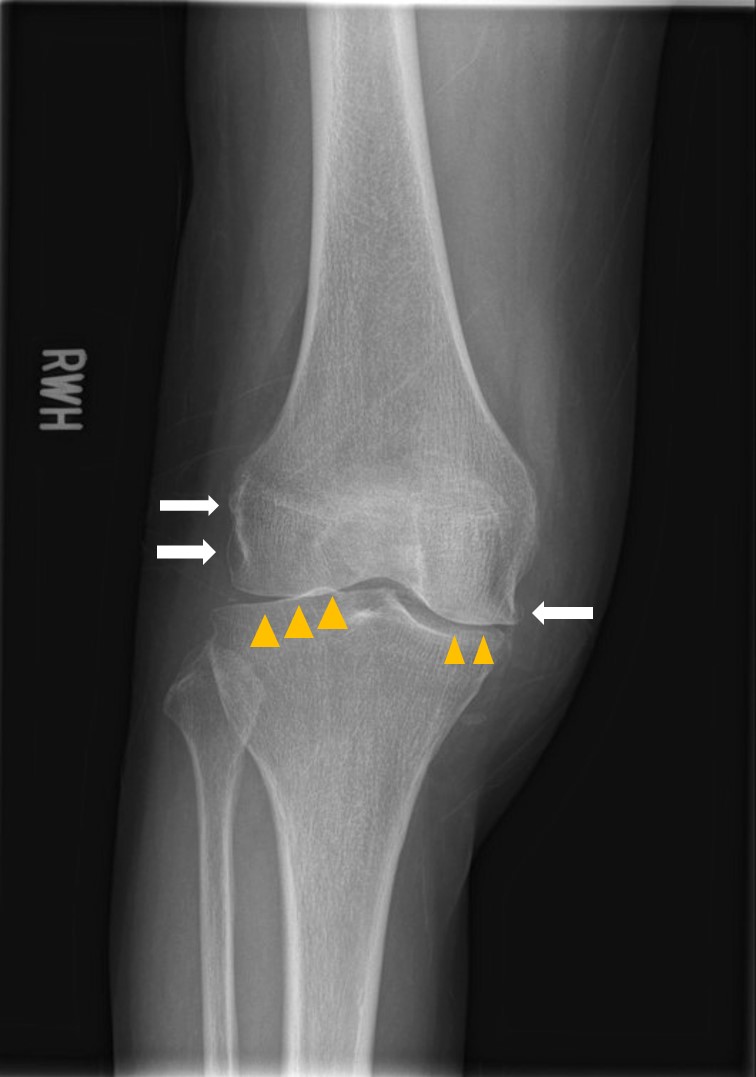

X ray image showed chondrocalcinosis over triangular fibrocartilage complex (TFCC) of right wirst (yellow arrow in Picture 2) and right knee (Picture 3). Asymmetrical joint space narrowing with spur formation (white arrow in Picture 4) of right knee was seen, compatible with OA change. No fracture or joint erosion seen over right elbow. (Picture 5).

Picture 4 Right Knee AP view